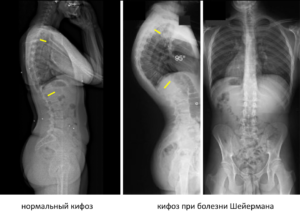

Основной внешний признак болезни Шейермана-Мау – это появление чрезмерного изгиба позвоночника назад в грудном отделе. Плечи отводятся вперед, лопатки несколько расходятся, а спина становится угловатой или дугообразно выгнутой.

Формируется позвоночный горб с вершиной ниже угла физиологического кифоза. Его отличие от нарушения осанки заключаются в том, что подросток с этой болезнью не может произвольно выпрямить позвоночник. Ведь при этом меняется форма позвонков, что приводит к стойкой кифотической деформации.

Даже при наклоне вперед и в положении лежа патологический изгиб сохраняется.

Диагностическими критериями болезни Шейермана-Мау являются характерные внешние симптомы, появление их в подростковом возрасте и рентгенологически подтвержденные изменения грудного отдела позвоночника.

При рентгенографии позвоночника важна боковая проекция. Для подтверждения диагноза юношеского кифоза должны быть выявлены следующие признаки:

- наличие кифотической деформации с углом кифоза более 45º;

- клиновидная деформация 3 и более позвонков (с сужением их передних отделов);